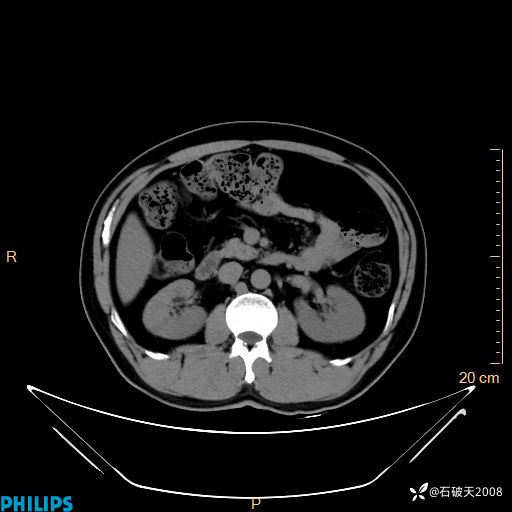

冠状位